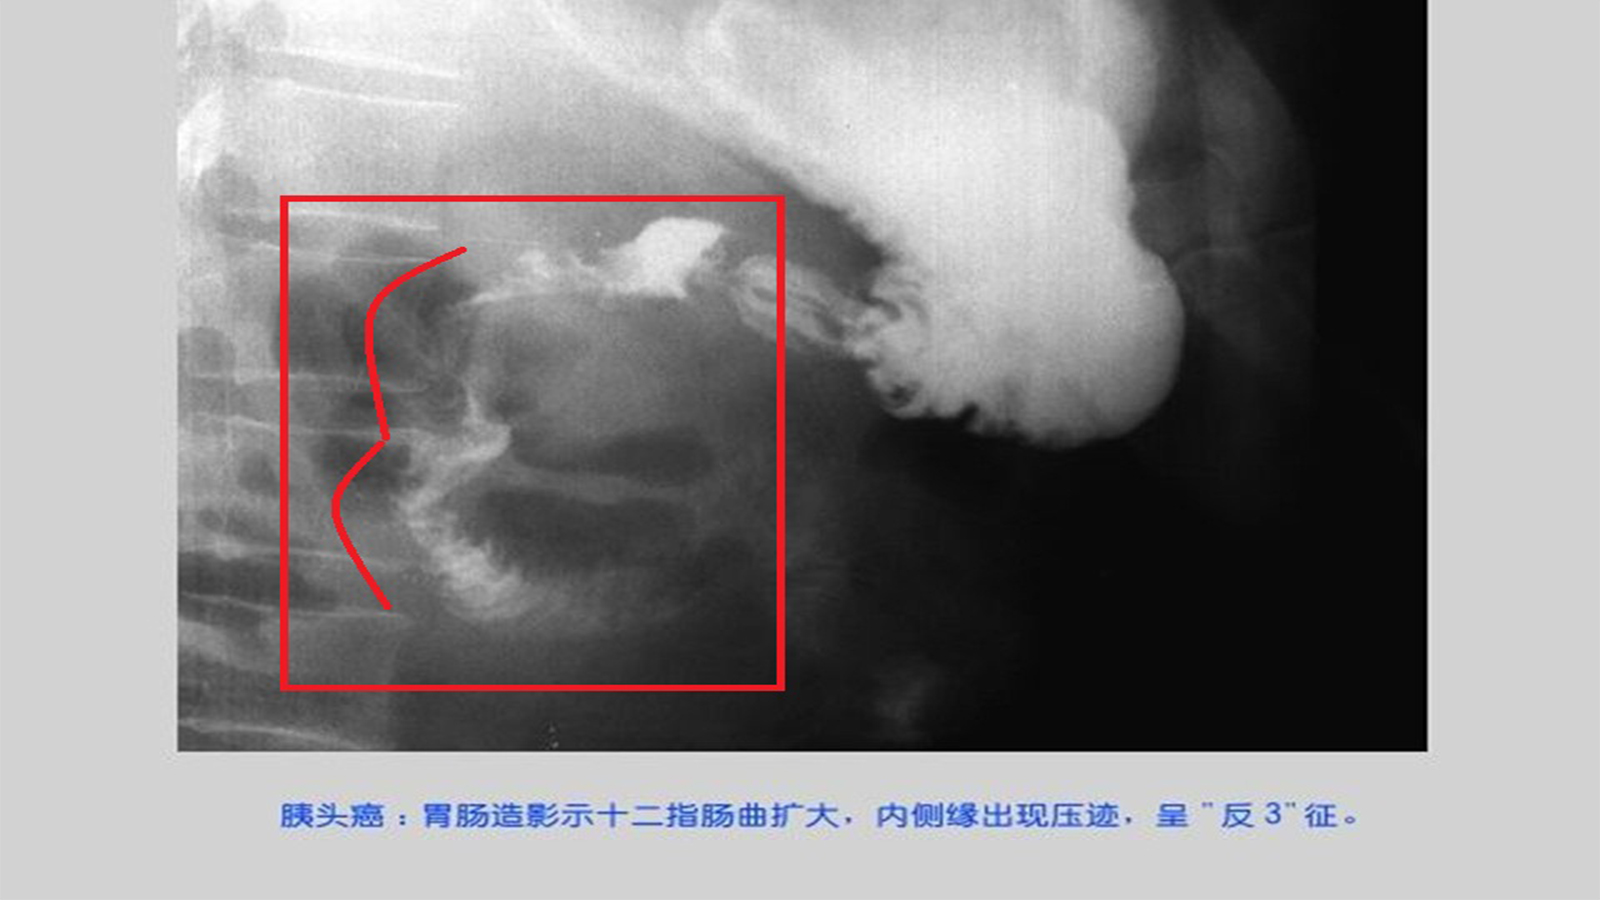

①低张十二指肠造影:在胰头癌晚期可见“反3字”征,为胰头癌肿块较大侵犯十二指肠时,可见十二指肠曲扩大,其内缘出现压迹,可呈双重边缘;亦可见于胰腺炎或胰头旁淋巴结肿大患者。